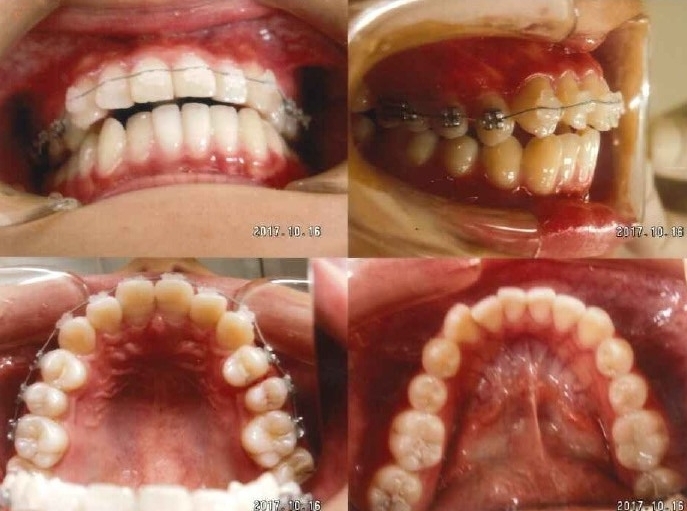

ケース1

-

治療前

-

治療後